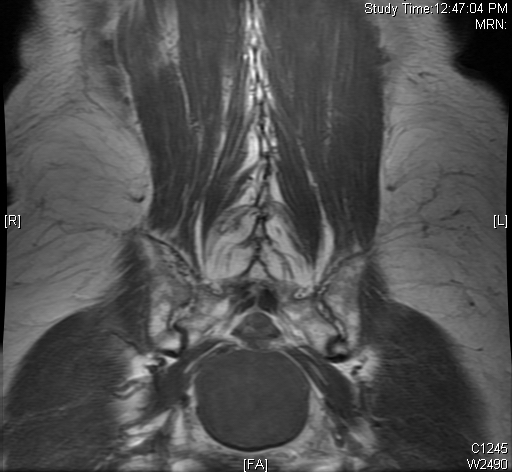

MRI (Fig. 4-10)

• Isointense or hypointense on T1W (Fig. 4-5)

• Hyperintense on T2W (Fig. 8 & 9)

• Hyper enhancement with gadolinium (Fig. 6 & 7).

Fig. 4-10: MR image of a chordoma shows a destructive bone lesion in the sacrum that is hypointense on T1W images, hyperintense signal on T2W and enhancement of the lesion after gadolinium.